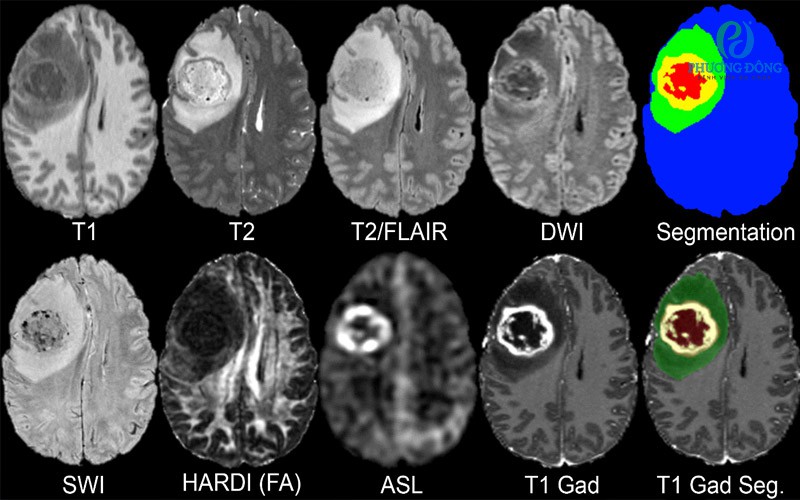

U não là một trong những bệnh lý nghiêm trọng của hệ thần kinh trung ương, có thể ảnh hưởng trực tiếp đến chức năng sống của con người. Các khối u trong não có thể là u lành tính hoặc u ác tính, và chúng có thể phát sinh từ nhiều loại tế bào khác nhau như tế bào thần kinh đệm, màng não hoặc các mô khác trong não. Ngoài ra, khối u có thể phát sinh từ chính mô não (u não nguyên phát) hoặc do tế bào ung thư từ các cơ quan khác di căn lên não. Việc phát hiện sớm và đánh giá chính xác đặc điểm của khối u đóng vai trò quan trọng trong việc lựa chọn phương pháp điều trị hiệu quả.

Trong các phương pháp chẩn đoán hiện nay, chụp cộng hưởng từ sọ não được xem là kỹ thuật hình ảnh tối ưu để đánh giá u não. So với các phương pháp khác như CT scan, MRI có khả năng hiển thị chi tiết mô mềm của não, giúp phát hiện các khối u ngay cả khi chúng còn ở kích thước nhỏ.

Một trong những vai trò quan trọng của MRI trong chẩn đoán u não là phát hiện sớm khối u. Nhờ độ tương phản cao giữa các mô não, MRI có thể nhận diện các vùng mô bất thường trong não, từ đó giúp bác sĩ phát hiện các khối u ở giai đoạn sớm. Điều này có ý nghĩa rất lớn trong điều trị, bởi nhiều loại u não nếu được phát hiện sớm có thể điều trị hiệu quả hơn.

Bên cạnh việc phát hiện khối u, MRI còn giúp xác định chính xác vị trí và kích thước của khối u. Hình ảnh MRI cho phép bác sĩ quan sát rõ mối liên quan giữa khối u và các cấu trúc quan trọng của não như thân não, tiểu não, hệ thống não thất và các mạch máu. Thông tin này rất quan trọng trong việc lập kế hoạch phẫu thuật, bởi phẫu thuật não đòi hỏi độ chính xác rất cao để tránh tổn thương các vùng chức năng quan trọng.

MRI cũng có vai trò quan trọng trong phân loại khối u não. Dựa vào đặc điểm hình ảnh, bác sĩ có thể phân biệt giữa các loại u khác nhau, chẳng hạn như u màng não, u thần kinh đệm hoặc u di căn não. Một số kỹ thuật MRI tiên tiến như MRI phổ (MR spectroscopy), MRI khuếch tán (DWI) hoặc MRI tưới máu (perfusion MRI) còn giúp đánh giá hoạt động chuyển hóa và mức độ tăng sinh của khối u, từ đó hỗ trợ phân biệt u lành tính và u ác tính.

Ngoài ra, MRI còn giúp đánh giá mức độ xâm lấn của khối u vào các mô não xung quanh. Điều này rất quan trọng trong việc xác định giai đoạn của bệnh và lập kế hoạch điều trị phù hợp như phẫu thuật, xạ trị hoặc hóa trị.

Sau khi điều trị u não, MRI tiếp tục đóng vai trò quan trọng trong việc theo dõi tiến triển của bệnh và phát hiện tái phát. Bác sĩ có thể so sánh hình ảnh MRI qua các lần chụp khác nhau để đánh giá hiệu quả điều trị và phát hiện sớm dấu hiệu tái phát của khối u.

Nhờ những ưu điểm vượt trội như khả năng hiển thị chi tiết mô não, độ chính xác cao và khả năng đánh giá nhiều đặc điểm của khối u, MRI đã trở thành công cụ không thể thiếu trong chẩn đoán và quản lý bệnh lý u não hiện nay.